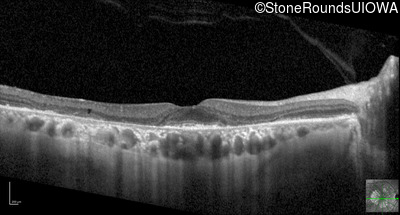

Optical Coherence Tomography - Left - 20/20 -2

Exemplar / OCT Stack

OCT Stack